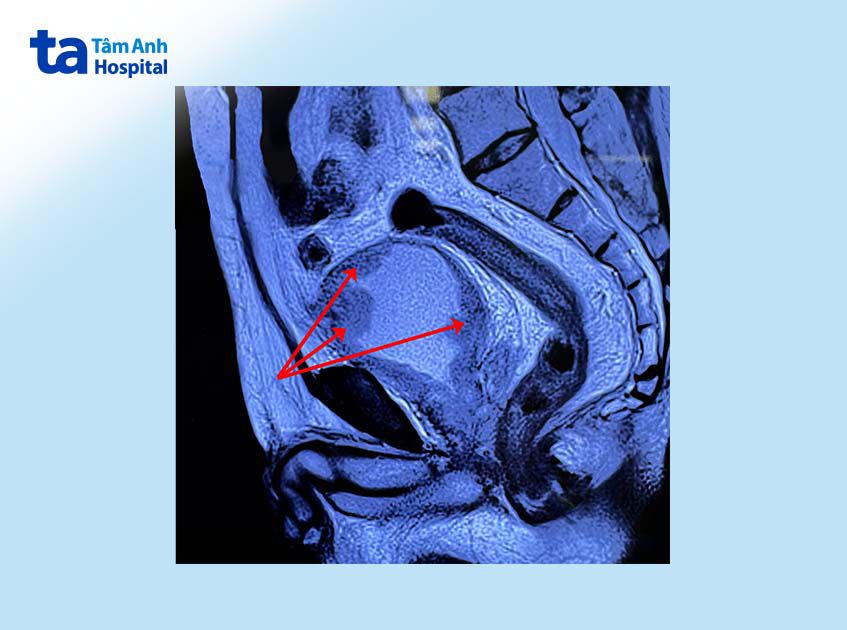

Qua thăm khám và chụp cộng hưởng từ (MRI) toàn thân, tiến sĩ bác sĩ Nguyễn Hoàng Đức, Trưởng khoa Tiết niệu, Bệnh viện Đa khoa Tâm Anh TP.HCM và Phòng khám Đa khoa Tâm Anh Quận 7, cho biết ông T. có nhiều khối u ác tính với kích thước khác nhau nằm rải rác trong bàng quang. Nghiêm trọng hơn, các khối u ác tính đã xâm lấn sâu xuống lớp cơ bàng quang và di căn sang một số hạch ở vùng chậu.

Tuy nhiên, ở trường hợp ông T., tế bào ung thư đã xâm lấn sâu vào cơ, đã di căn đến cổ bàng quang và niệu đạo nên không thể áp dụng phương án này. Phương án tối ưu là phẫu thuật cắt toàn bộ bàng quang, nạo vét hết các hạch di căn, rồi dùng ruột non để chuyển lưu nước tiểu từ thận trực tiếp ra ngoài cơ thể qua một lỗ nhỏ ở thành bụng.